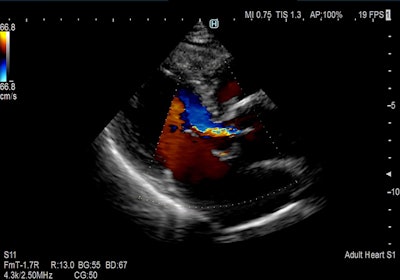

Hitachi is exhibiting three ultrasound scanners: Arietta 850 SE, Arietta 65, and Arietta 50. Arietta 850 SE is an upgraded version of Arietta 850 and features a 23-inch LCD monitor, shear-wave measurement and real-time tissue elastography for the assessment of liver stiffness, and Real-time Virtual Sonography, which offers image fusion for interventional procedures. Arietta 65 features Smooth Workflow and Superb Imaging tools and is useful for real-time elastography and auto intima-media thickness (IMT) measurement, while Arietta 50, the most compact model of the series, features a 21.5-inch monitor and can be used across various applications.

Color flow cardiac image acquired on Arietta 65 system. Image courtesy of Hitachi.The company is also demonstrating Futus, another compact system that supports auto IMT and elastography, as well as ob/gyn applications.